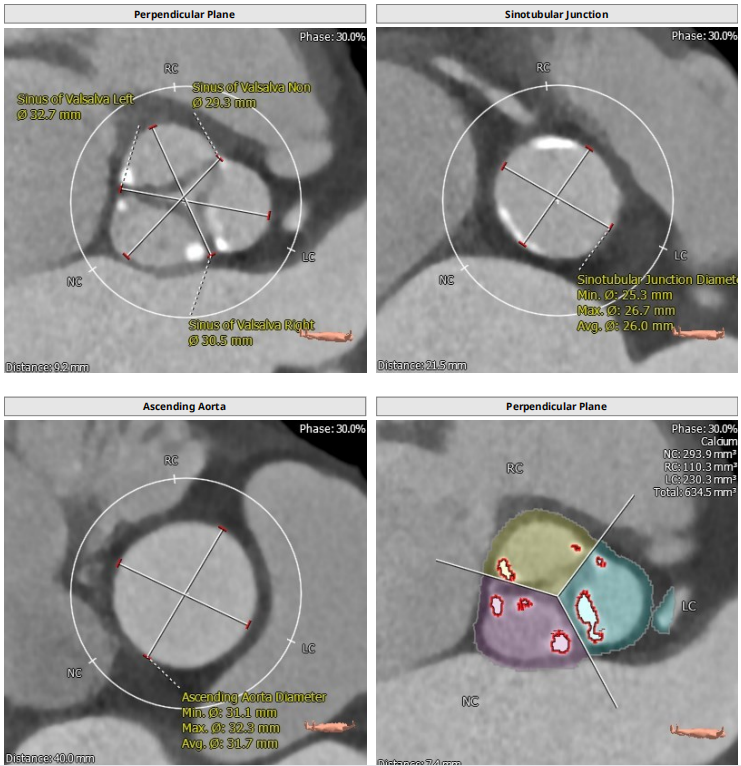

根部解剖: